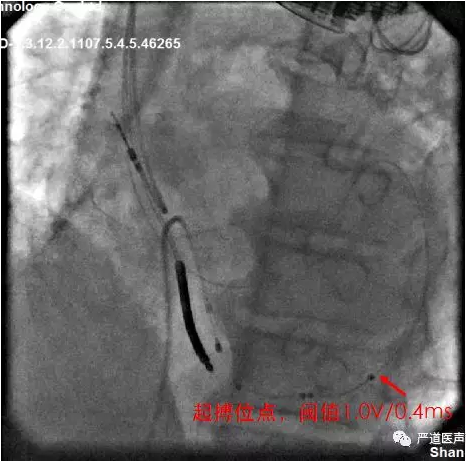

● 使用成锐角的鞘中鞘置入左室四级电极于远端。

● 130度鞘中鞘指的是外角130度,所以成角为锐角60度。

● 为了固定将四级电极送的比较远,此时发现LV1点靠近心尖部,四级电极优势体现,植入心尖,起搏侧壁,起搏向量选择LV4to RVcoil。